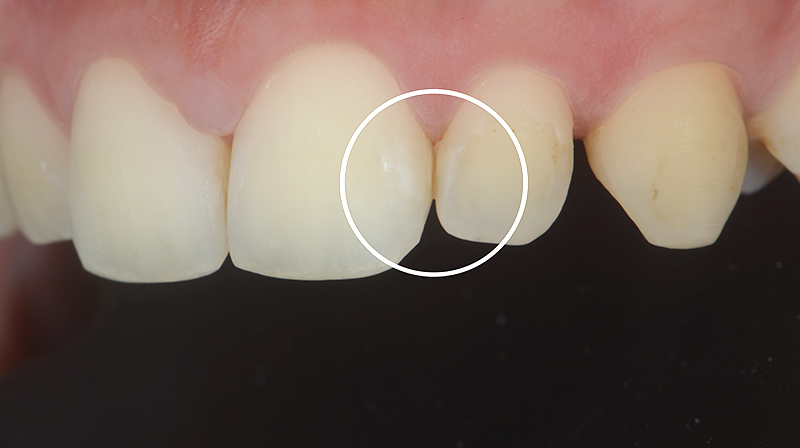

CASO CLINICO 2 - Lesione cariosa iniziale prossimale adiacente ad un intervento restaurativo di seconda classe.

In una paziente di 30 anni, durante un esame radiografico di routine viene rilevata una lesione cariosa interprossimale cavitata sul 36 mesiale ed una lesione cariosa interprossimale non cavitata sul 35 distale coinvolgente radiologicamante la metà interna dello smalto (E2, Fig. 7 e Fig. 8).

In fase di trattamento restaurativo del 36 mesiale, la paziente viene trattata con una singola applicazione di CURODONT™ REPAIR sul 35 distale. Una volta concluso il trattamento, alla paziente vengono fornite le istruzioni di igiene orale di routine e le viene consegnato un tubetto di CURODONT™ PROTECT (Fig. 9). Sei mesi dopo il trattamento, alla visita di follow-up, si osserva radiologicamente la regressione della lesione.

Fig. 8 - Immagine della lesione prima dell’applicazione di CURODONT™ REPAIR.